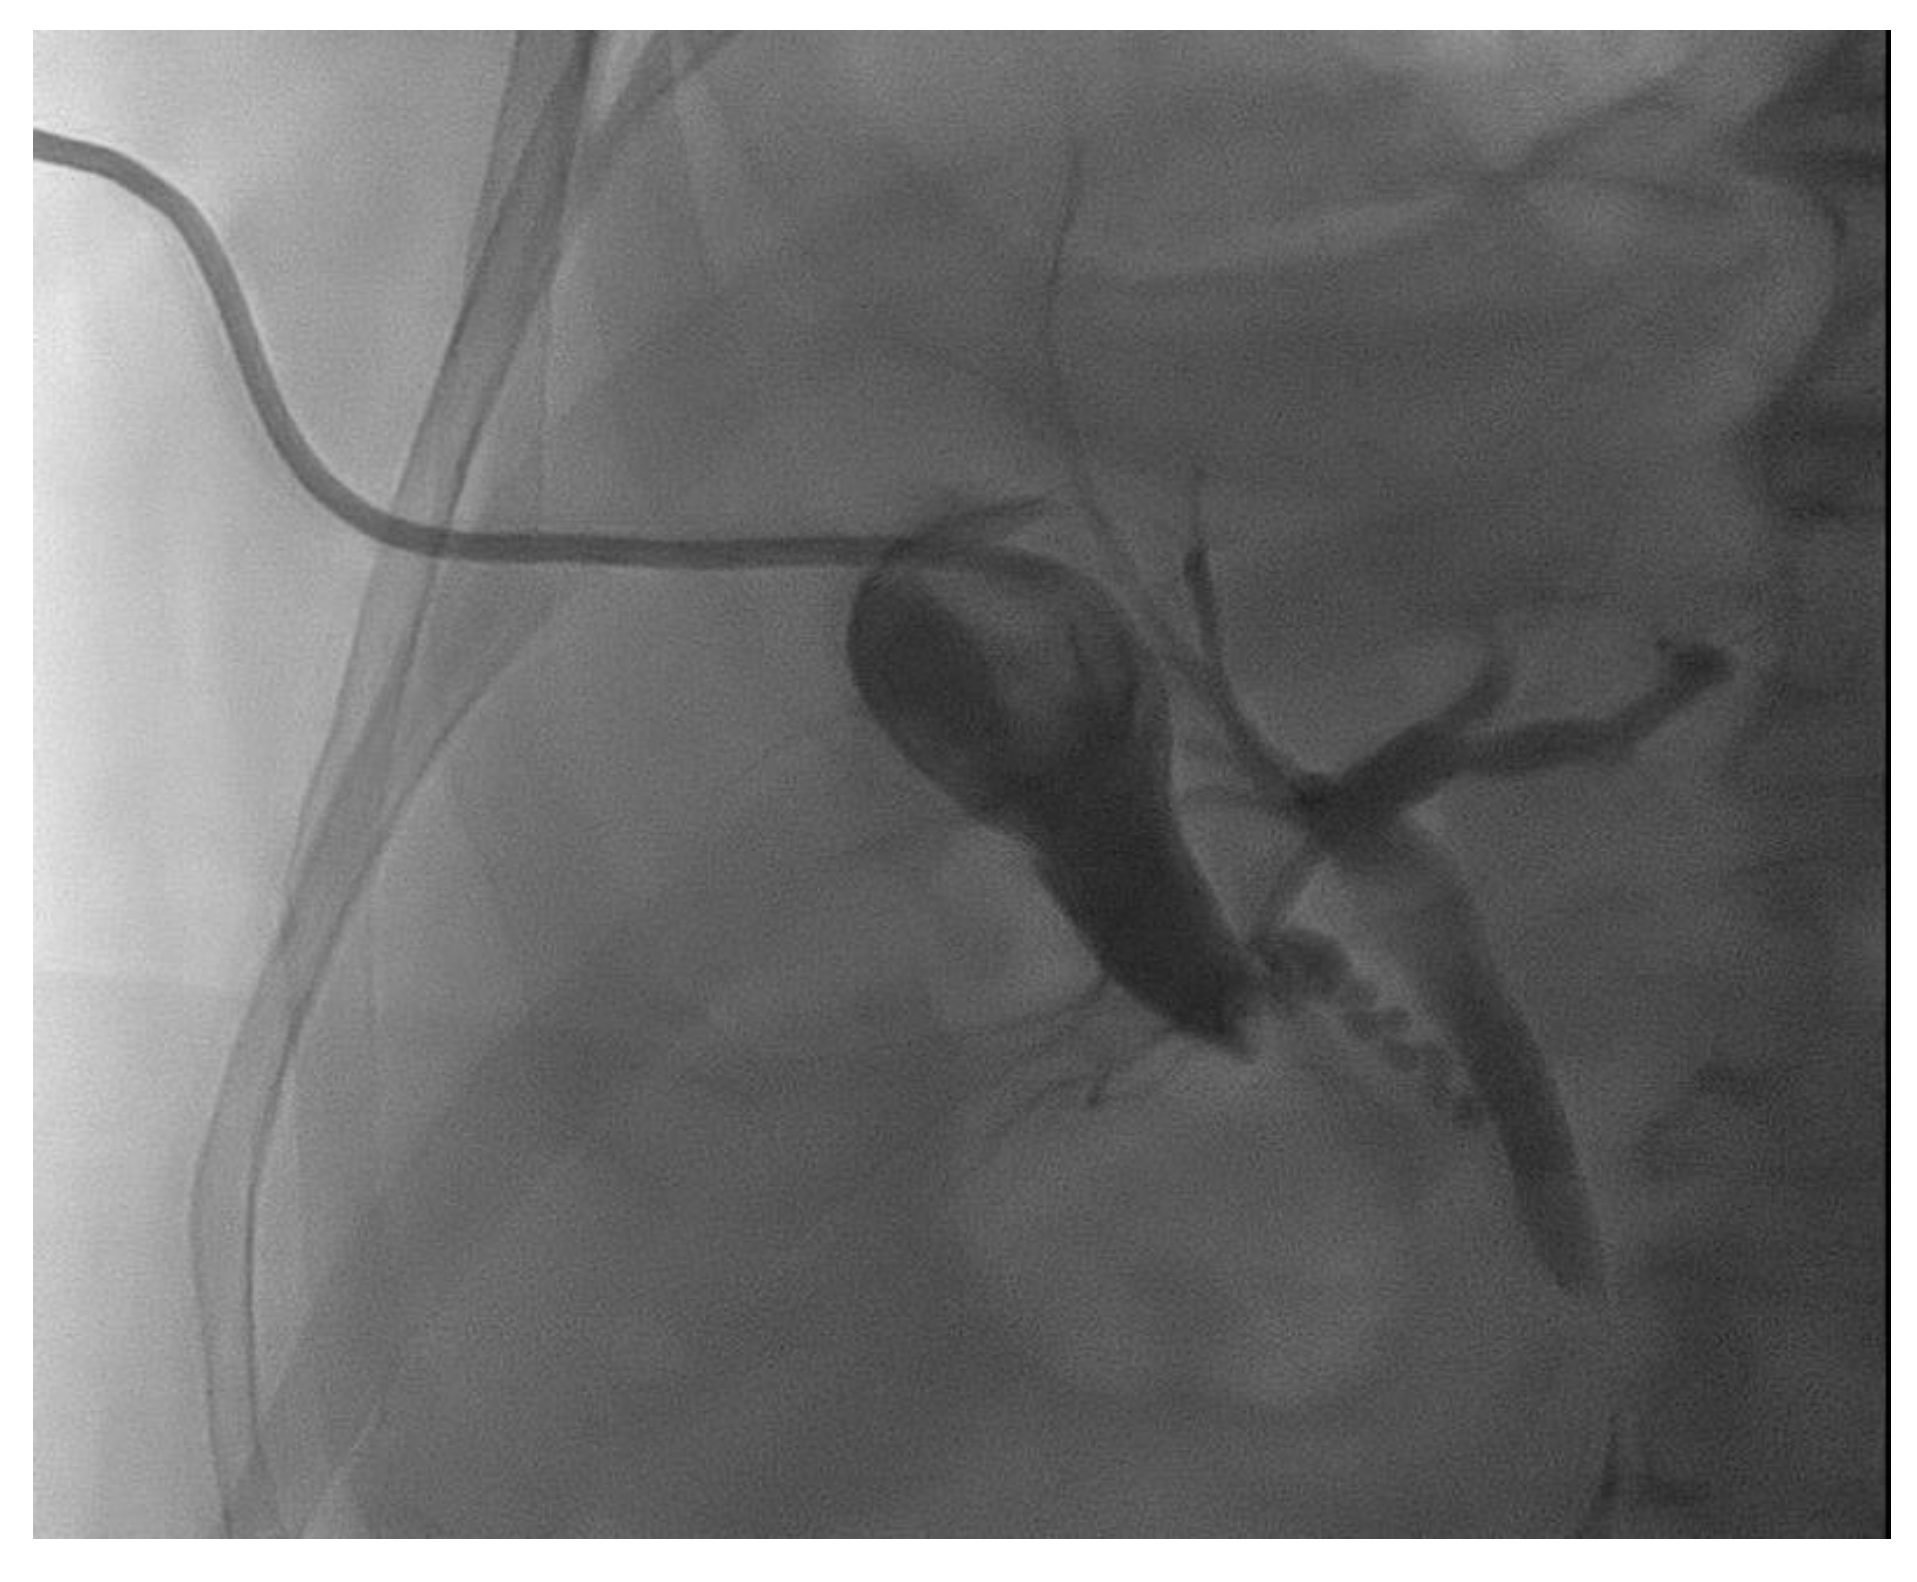

2. Transpapillary Endoscopic Gallbladder Drainage: Technical Aspects